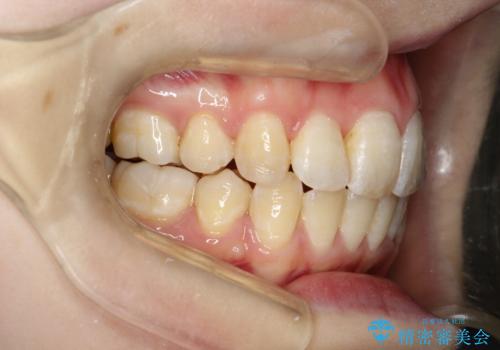

上下前歯が接触しない オープンバイトをインビザラインで改善

オープンバイト(開咬)を非抜歯インビザラインで治す